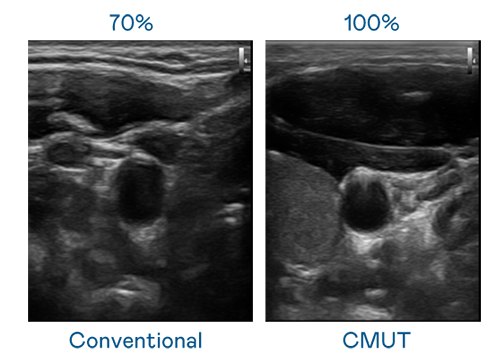

CMUT 技术是一种用电容式微机电元件来产生超音波讯号的技术。与传统 PZT 压电式技术相比,CMUT 频宽增加 30%,更宽频的超音波讯号让影像解析度大幅提升,是实现高影像品质医疗超音波扫描、促进精准医疗发展的关键技术。

大频宽带来超清晰影像

超音波影像的解析度高低,首先取决于探头能发出的讯号频宽。J9九游 CMUT 可提供高清晰的超音波讯号,提供高频宽、高灵敏度、影像纹理细节更高的超音波影像,协助医护人员缩短影像判读时间及利用精准的医疗影像进行诊断。